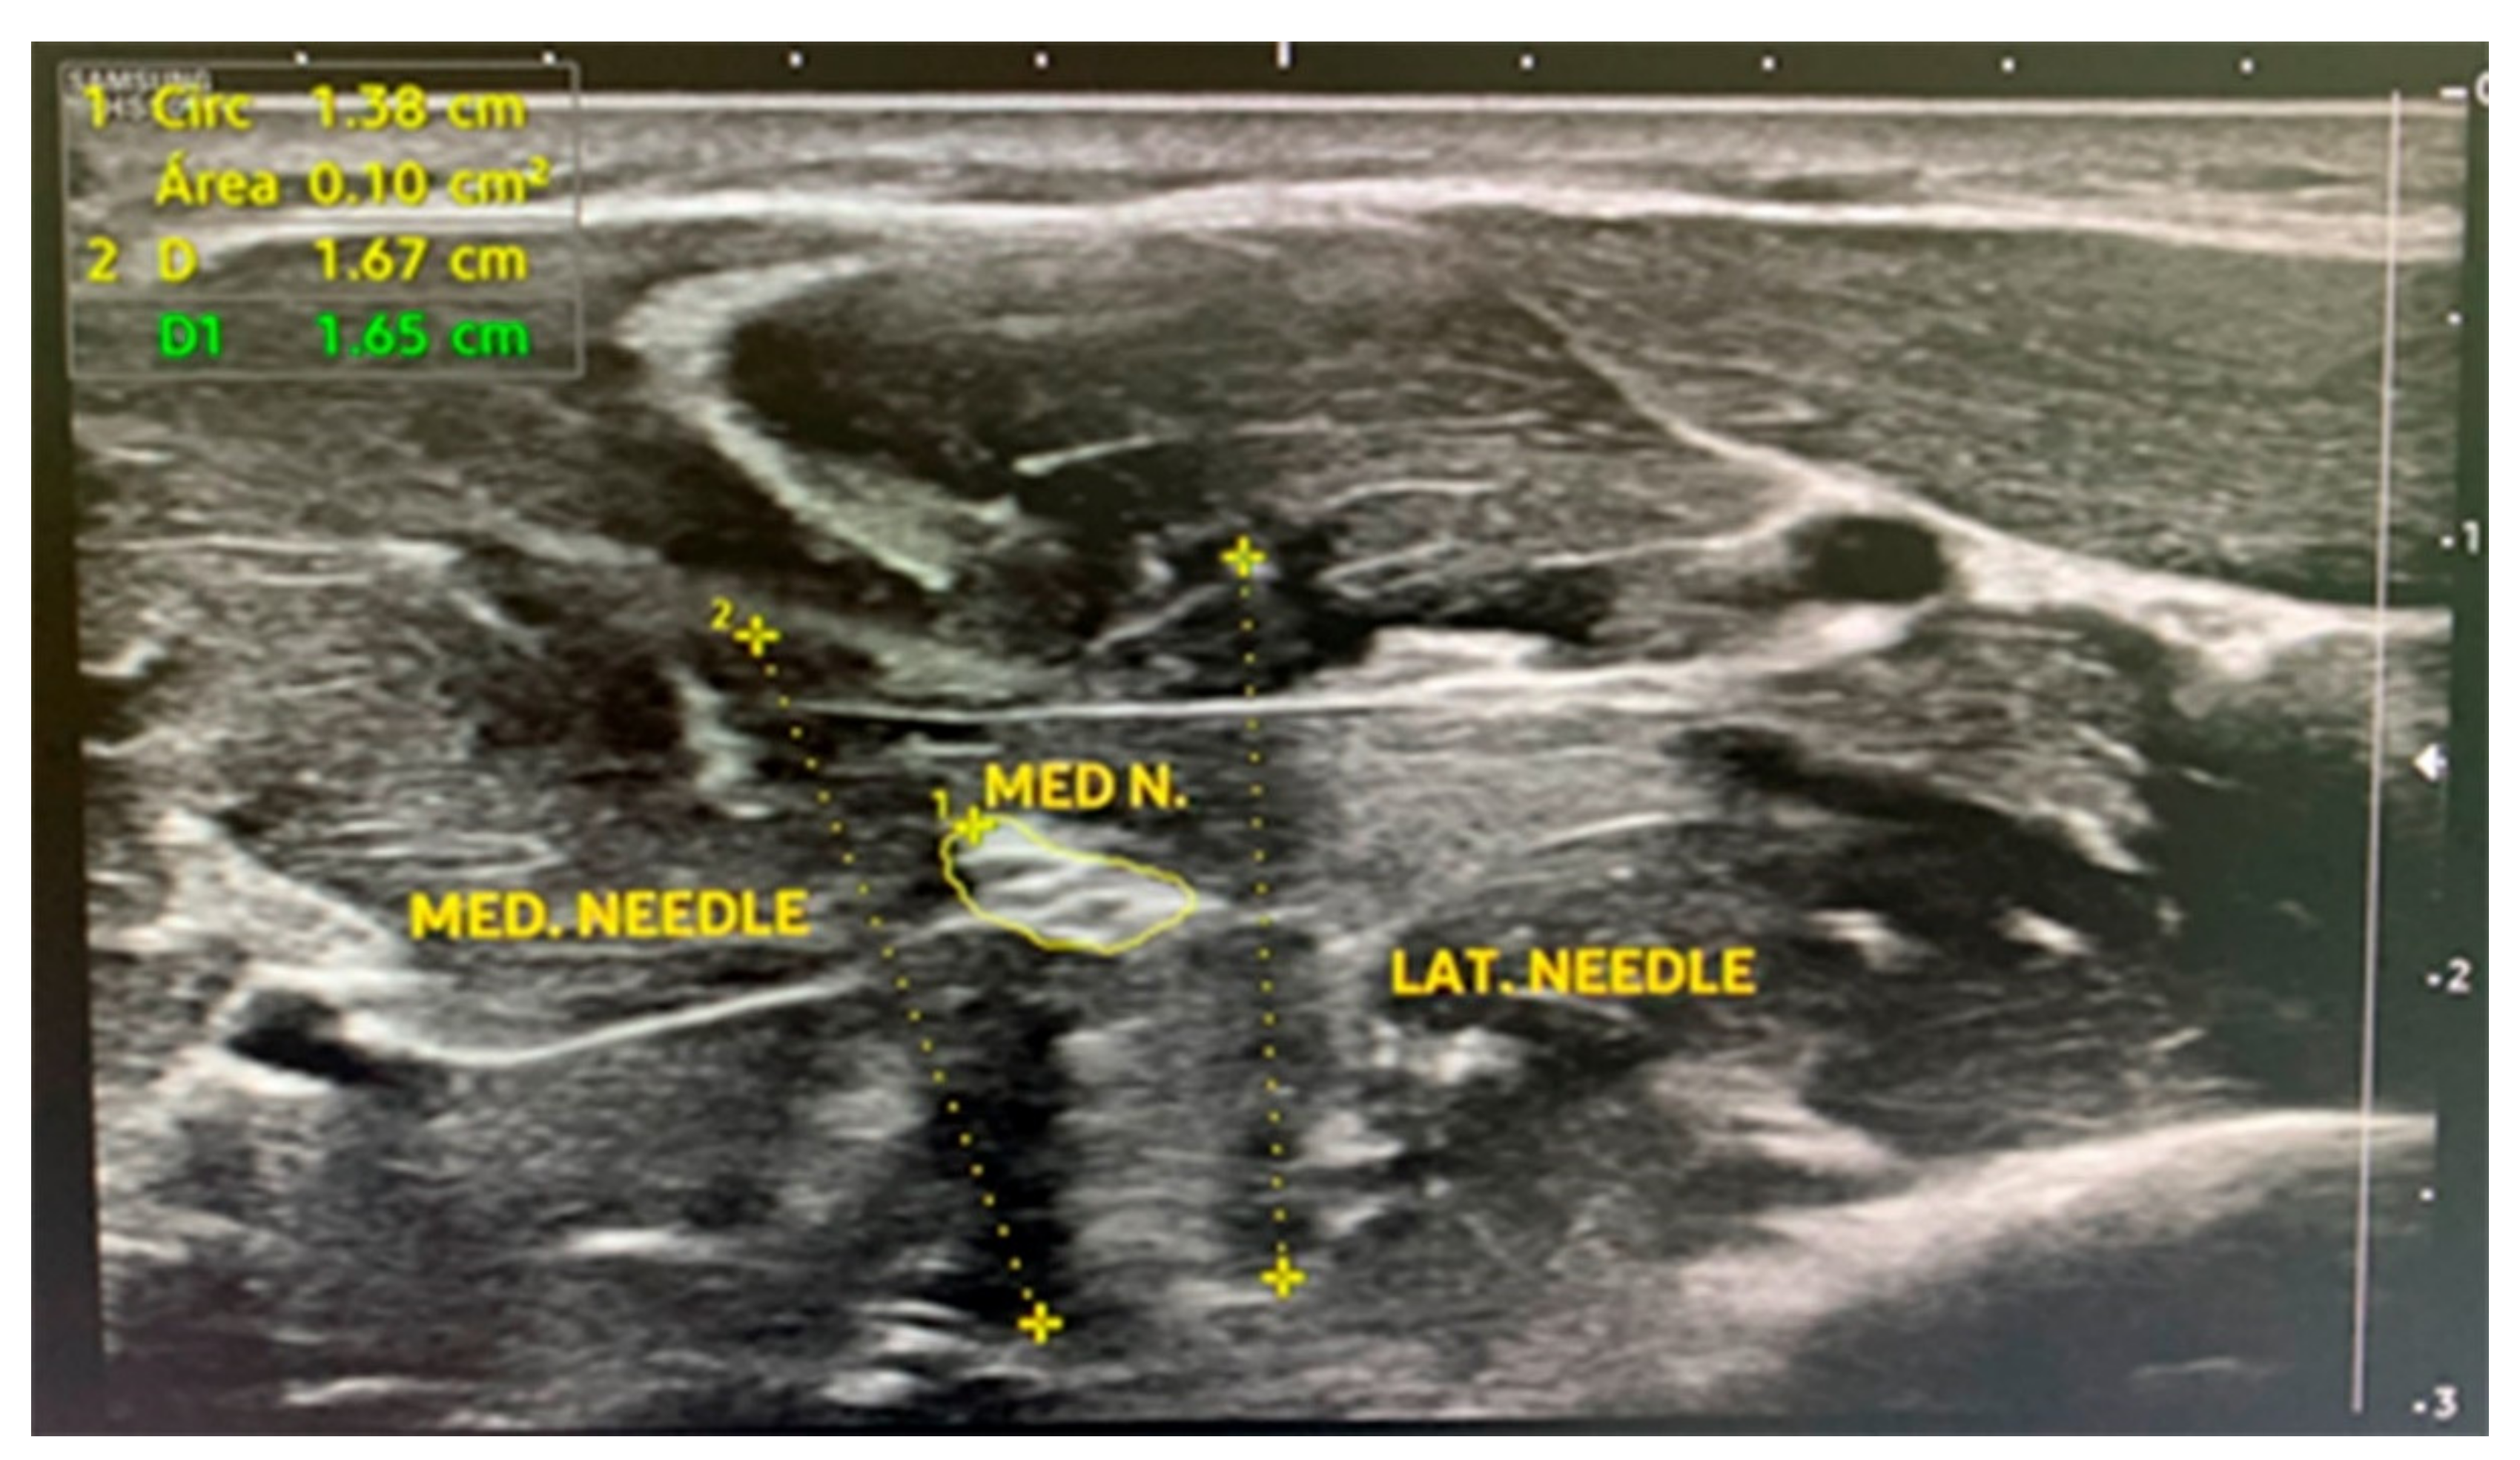

2.3. Intervention